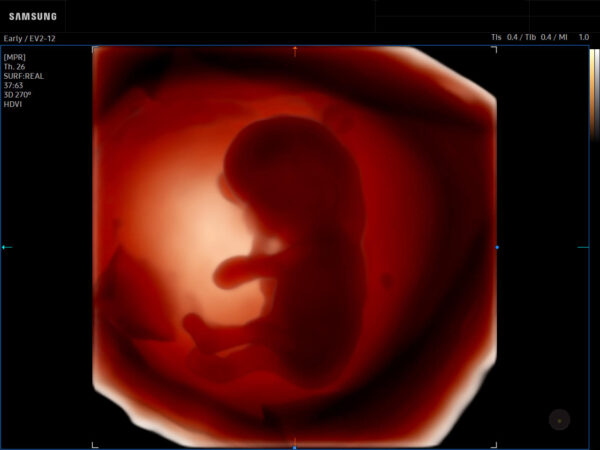

Samsung Medison, a global medical equipment company and affiliate of Samsung Electronics, has launched the all-new Samsung Z20 in the U.S. – a premium AI-powered ultrasound system designed for Advanced Ob-Gyn applications. The Z20 made its U.S debut at the Society for Maternal-Fetal Medicine (SMFM) 2025 in Denver, Colorado. The Z20 introduces innovations aimed at overcoming various diagnostic challenges such as high-BMI patients, and operator variability, compounded by staffing shortages which impact exam quality and efficiency.

The Z20’s groundbreaking imaging performance improves diagnostic accuracy, even in challenging cases such as high-BMI patient. Powered by Samsung’s Next-Generation Crystal Architecture TM the new imaging engine eliminates technical barriers by incorporating advanced software beamforming.